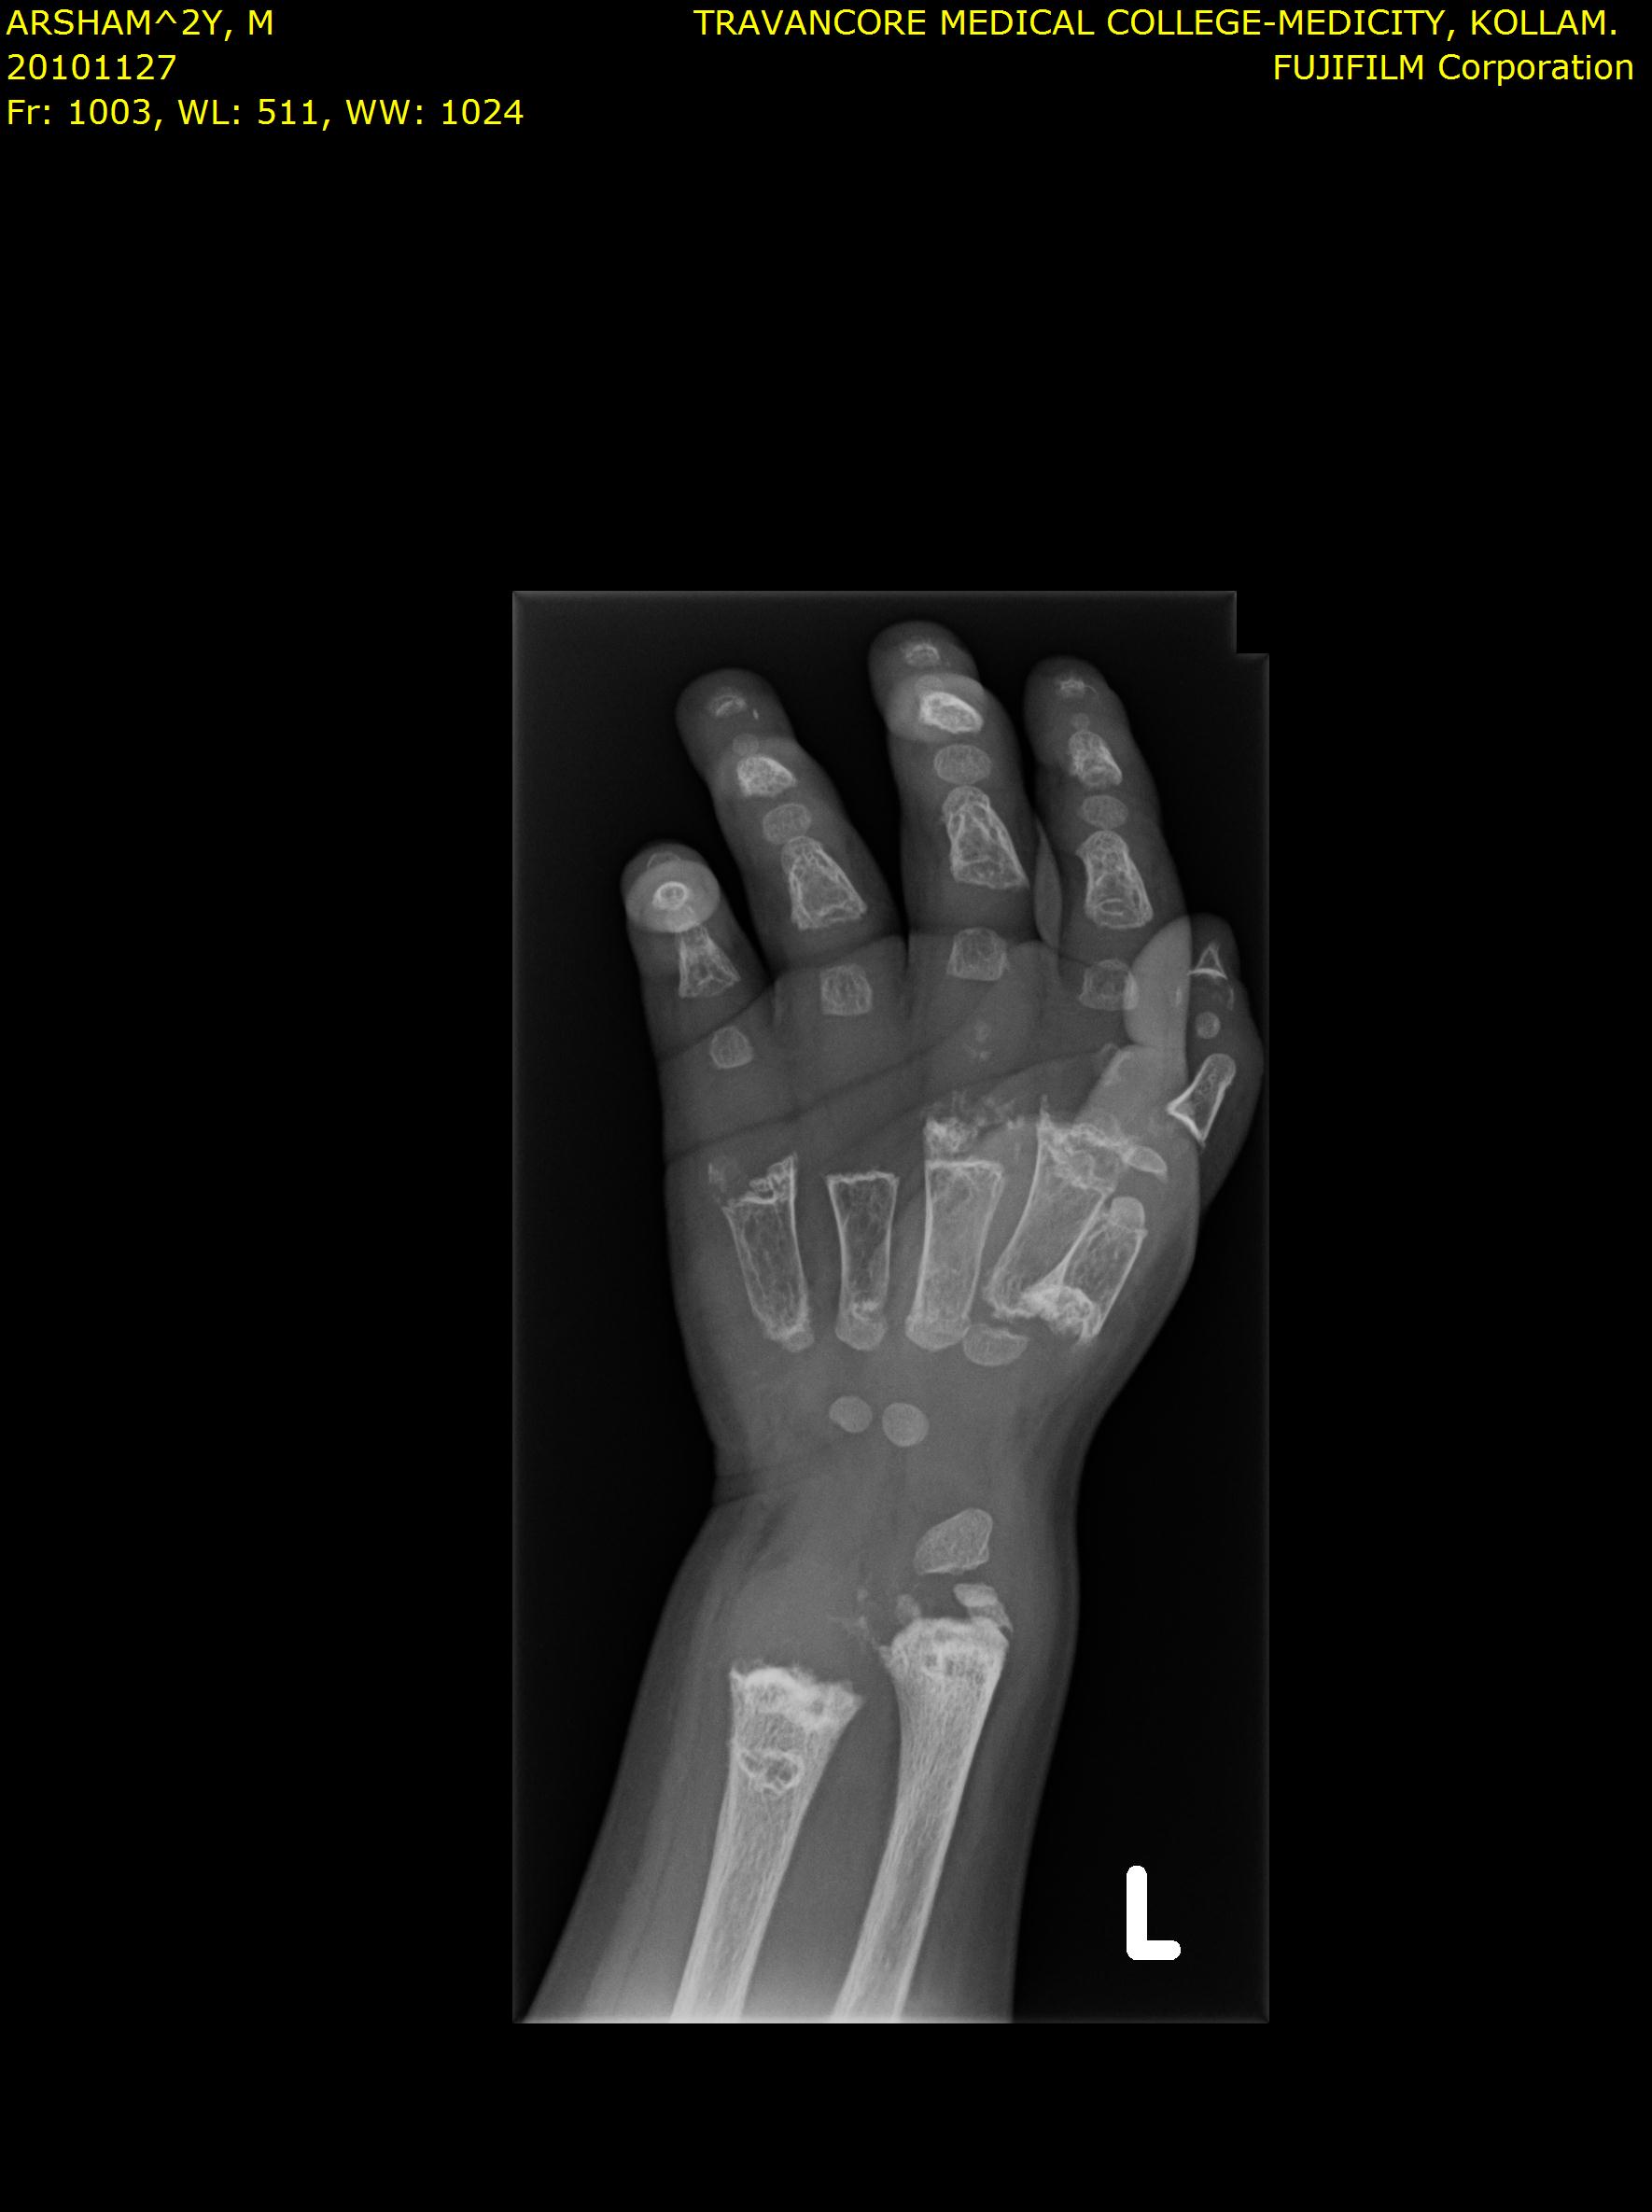

Here we share radiographic images to help with diagnosis of Jansen's disease:

Jansen's patients show extreme disorganization of the metaphyses of the long bones and of the metacarpal and metatarsal bones in sharp contrast to the almost normal appearance of the epiphyseal centers, which on x-ray appear widely separated from the long bones. The chin is receding. The fingers, especially the distal phalanges, are very short. The spine, pelvis, and lower legs are distorted.